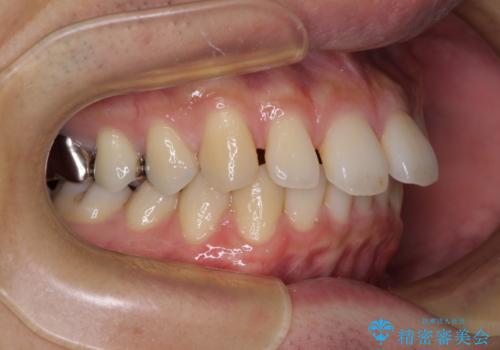

深い咬み合わせと前歯の隙間 ハーフリンガルによる矯正治療

- 咬み合わせにより上顎正中に隙間ができているとのことで来院された患者様です。

インビザラインは自己管理が煩わしく、表側のワイヤー装置は目立つので避けたいとのことで、上顎だけが裏側装置のハーフリンガルにて矯正治療を行うこととしました。